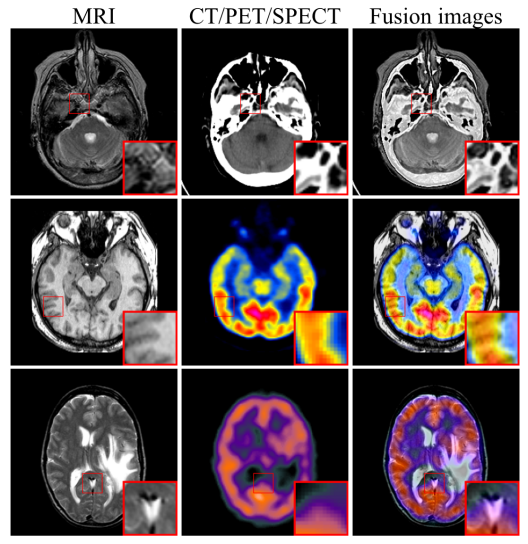

医学影像是临床诊断的重要手段,由于解剖结构影像和功能影像的成像原理不同,单模态医学影像的信息存在着局限性。通过图像融合技术将不同模态的医学影像融合在一起,实现不同模态间互补信息和突显优势,增强影像信息量,有助于更准确诊断和有效治疗。

此外,为进一步有效地保留医学影像的纹理特征和强度信息,定义了包含内容损失和强度损失的联合损失函数来约束融合模块,并引入自适应权重来控制源图像的信息保留程度。所提出的框架在CT-MRI、PET-MRI和SPECT-MRI等多个融合任务上进行实验,通过定性和定量分析验证了模型的优越性。